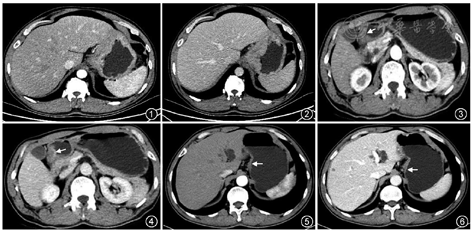

胃癌分化程度与肿瘤的生物学行为以及患者预后等方面密切相关,准确评估其分化程度有助于指导临床制定个体化治疗方案以及判断患者预后。胃癌病灶的CT强化方式及强化率与胃癌的分化程度存在一定的相关性,分层或不均匀强化者,组织分化多为低分化腺癌(图1,2),均匀强化者组织分化多见于高或中分化腺癌[1](图3, 4, 5, 6)。文献报道[2],高分化腺癌动脉期强化率(增强扫描与平扫CT值差值/肿瘤平扫CT值)≥0.5,实质期强化率≥1.0;中分化腺癌实质期强化率<1.0,动脉-实质期强化率(增强实质期与平扫CT值差值/动脉期与平扫CT值差值)<2.0;低分化腺癌实质期强化率≥1.0,动脉-实质期强化率≥2.0。需要指出的是,目前以CT增强特征预测胃癌分化程度的研究尚存在一定的分歧[3, 4],仍需对更多成像方法诸如灌注成像、能谱成像、影像组学等进一步研究。